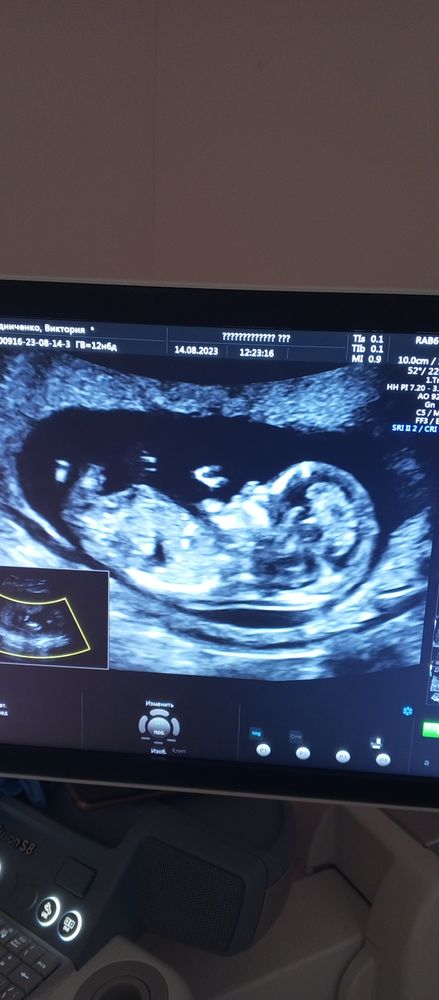

Вот и дождалась я его 😋 было очень волнительно, так как токсикоза у меня не было в эту беременность я очень переживала, что скажут нет сердцебиения. Но слава богу мы на неделю бежим вперед) по м 12.6 недель, по УЗИ 13,4) к сожалению пол точно не смогли определить, очень уж стеснительный малыш ☺ может есть предположения?)